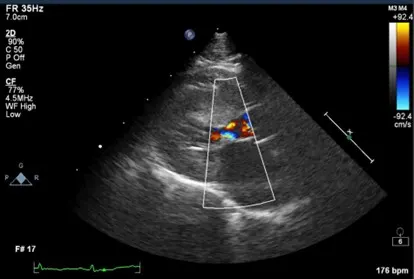

At the 4-month follow-up, the owner reported Drew was doing well overall but had short periods of heavy breathing associated with play activity. The sleeping respiratory rate was 32 to 36 breaths per minute at home. The murmur was unchanged. Echocardiogram results showed that the hypertrophic cardiomyopathy was stable and the thrombus was markedly improved and had decreased from 1 large thrombus in the auricular appendage to 2 small thrombi (1 in the atrial chamber and 1 in the appendage, along with spontaneous echo contrast [ie, smoke]; Figure 2). Clopidogrel, rivaroxaban, and enalapril were prescribed lifelong, with regular rechecks that include blood work and blood pressure measurement.

FIGURE 2 Stable left ventricular hypertrophy 4 months following diagnosis. Systolic anterior motion of the anterior mitral valve leaflet can also be seen.